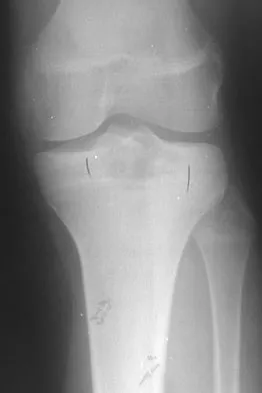

Figure 3 shows the AP radiograph of a patient with diabetes mellitus who has knee pain. A semiconstrained knee prosthesis was used in this patient to prevent which of the following complications?

Explanation

The radiographic appearance of the joint is highly suspicious for neuropathic joint (Charcot's joint). Evidence of bone loss on both the tibial and the femoral sides may necessitate the use of metal and/or bone augments. Patients with a neuropathic joint often have excellent range of motion, and postoperative stiffness is not a problem. The main problem with these patients is instability that occurs secondary to ligamentous laxity. Use of a semiconstrained prosthesis prevents the latter complication. Parvizi J, Marrs J, Morrey BF: Total knee arthroplasty for neuropathic (Charcot) joints. Clin Orthop 2003;416:145-150.